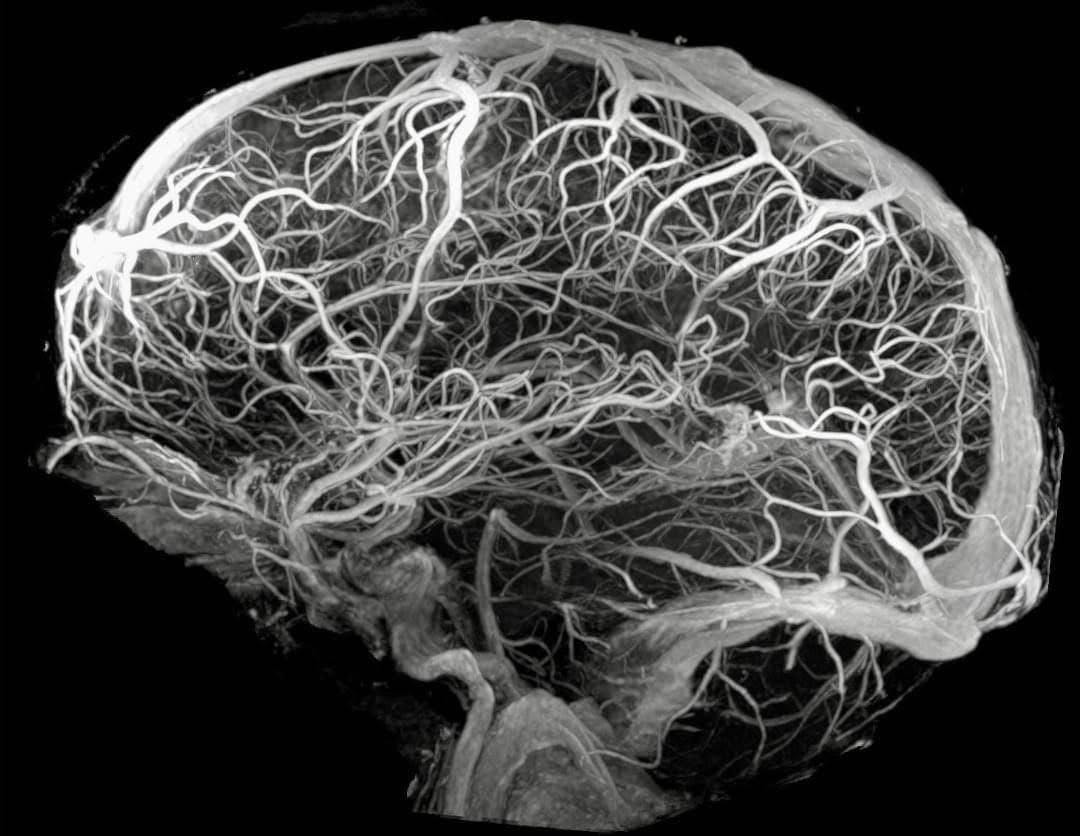

ออกกำลังกาย แก้ปัญหาแทบทุกหลอดเลือดที่จะเป็น ‘จุดหายนะ’ ให้เกิดหลอดเลือดสมองตีบ บทความนี้จะชี้ให้เห็นจะจะ ทุกเส้น ทุกจุด เพื่อให้เห็นว่าการออกกำลังกายมันซื้อหลักประกันระยะยาวว่า โอกาสที่คุณจะนอนอัมพาตบนเตียง ต่ำลงมากๆ จริงๆ

ความจริงที่คนส่วนใหญ่ไม่ค่อยทราบคือ หลอดเลือดสมองตีบนั้น (Ischemic stroke) เกิดได้หลายจุดมาก และหลายครั้งมาในรูปลิ่มเลือดที่ลอยมาอุด ในขณะที่ถ้าไปดูภาวะหลอดเลือดหัวใจตีบ มักจะเกิดจากหลอดเลือดหัวใจเองเลยเป็นหลัก

นั่นเลยทำให้มี ‘ช่องโหว่’ มากมาย ที่ทำให้สมองของเราตั้งอยู่บนความเสี่ยง สมองของเราที่ทำแทบทุกอย่างให้เราเป็นเรา ขยับเคลื่อนไหว รับความรู้สึก รับภาพ รับเสียง อารมณ์ พฤติกรรม และอีกสารพัด ที่ไม่รู้ว่าเกิดโรคสมองขาดเลือดมันจะสุ่มโดนจุดไหน

กลุ่มนี้เป็นหลอดเลือดที่เริ่มจาก วงเวียนหลอดเลือดแดงฐานสมอง (Circle of Willis) แล้วแตกแขนงเป็น 3 เส้นหลัก หน้า (ACA), กลาง (MCA), หลัง (PCA) และเส้นอื่นๆ อีก

จุดนี้เป็นจุดเสี่ยงที่ LDL ที่ขนส่งคอเลสเตอรอล กับเม็ดเลือดขาว สามารถแทรกไปในผนัง ไปกินกันจนอักเสบ แล้วก็พอกคอเลสเตอรอลไปเรื่อยๆ กำเนิดคราบไขมัน (plaque) ทีละน้อยทีละน้อย

จนวันหนึ่งมันตีบพอที่เลือดไหลผ่านแล้ว มันจะเสียดสีที่ผนังแรง เหมือนเราเอามือบีบปากสายยาง น้ำก็จะยิ่งไหลแรง ถูนิ้วเราแรง นั่นแหละค่ะ หลอดเลือดที่ตีบก็โดนแบบนั้น จนวันนึงมันฉีกเป็นแผล ลิ่มเลือดก็เกิดขึ้นทันที อุดหลอดเลือดแบบเฉียบพลัน แล้วก็สมองขาดเลือดทันที (Stroke)